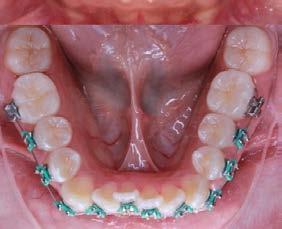

Caso clínico: paciente femenino de 19 años, patrón dolicofacial, perfil convexo, clase II esqueletal debido a una retrusión mandibular, mordida abierta anterior esqueletal, clase II molar, clase canina no establecida por mordida abierta, apiñamiento severo superior e inferior y deglución atípica.

Resultados: obtención de una clase canina I y clase molar II funcional, se corrigieron las sobremordidas horizontal y vertical, y se logró la coincidencia de líneas medias facial y dental. El manejo de la mordida abierta anterior se llevó a cabo por medio de la corrección del hábito de deglución atípica con la ayuda de spikes de resina, elásticos intermaxilares y arcos utility, y se obtuvieron buenos resultados estéticos, dentales y funcionales.